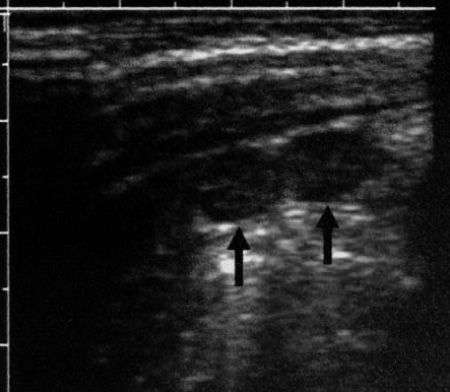

К дополнительным ультразвуковым критериям аппендицита можно отнести усиление кровотока в толще стенки неперфоративного червеобразного отростка (при проведении цветовой допплерографии), а также визуализацию периаппендикулярного жира (фото 4). Могут определяться периаппендикулярные воспалительные изменения, газ или жидкость (фото 5). В некоторых случаях визуализируются эхогенные фекальные конкременты, которые дают акустическую тень. Также может наблюдаться большое количество увеличенных брыжеечных лимфоузлов (фото 6).

Фото 6. Увеличенные мезентериальные лимфоузлы. Поперечное ультразвуковое изображение нижнего правого квадранта живота: стрелками обозначены увеличенные лимфатические узлы